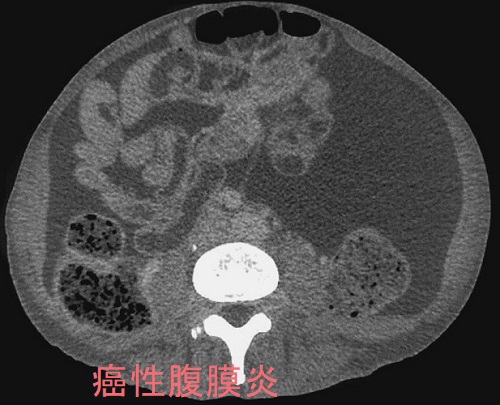

甲状腺機能低下症の4%未満に腹水(蛋白濃度が高い粘液水腫性腹水)。粘液水腫性腹水自体が腹膜を刺激し、卵巣癌の腫瘍マーカーCA125 の産生を増加させる。甲状腺ホルモン(チラーヂンS)補充療法により腹水は消失し、約1カ月遅れてCA125も正常値に。特に甲状腺ホルモン値(FT4,FT3)が低いと粘液水腫性腹水(腹水穿刺・利尿剤に反応悪く改善に時間を要す)・胸水(利尿剤で速やかに消失)・心嚢液(肺水腫、呼吸困難、右心不全、陰嚢・両下腿浮腫)貯留、腸管浮腫[甲状腺ホルモン剤(チラーヂンS)吸収障害]が出現。甲状腺乳頭癌、甲状腺未分化癌の腹膜播種がある。

粘液水腫性腹水自体が腹膜を刺激し、卵巣癌の腫瘍マーカーであるCA125 の産生を増加させると考えられます。大量の腹水があって、血清CA125も異常高値なら卵巣癌の腹膜びまん性転移(癌性腹膜炎)を疑いますが、実は卵巣癌ではなく甲状腺機能低下症が原因なのです。報告では血清CA125が822 U/mL(<35 U/mL)まで上昇したそうです。